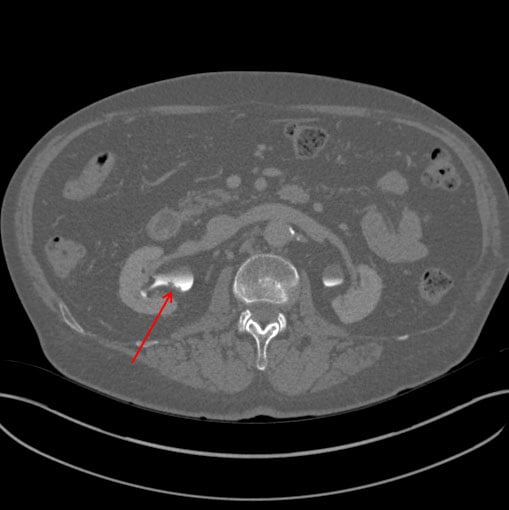

Thanks to Dr.s Goldstein and Bennett for picking up the subtle R renal collecting system abn on the vascular CT- my resident and I struggled to see these filling defects they were so subtle.

We just took him to OR- he indeed had a tumor in the renal pelvis. We ablated with laser- there is a relatively high likelihood it will recur – but will attempt conservative therapy with laser ablation/surveillance to avoid need for nephrectomy (history CRI).

Had this lesion been missed on the CT no doubt the tumor would have grown undetected (he had zero symptoms) until it was too large to ablate.